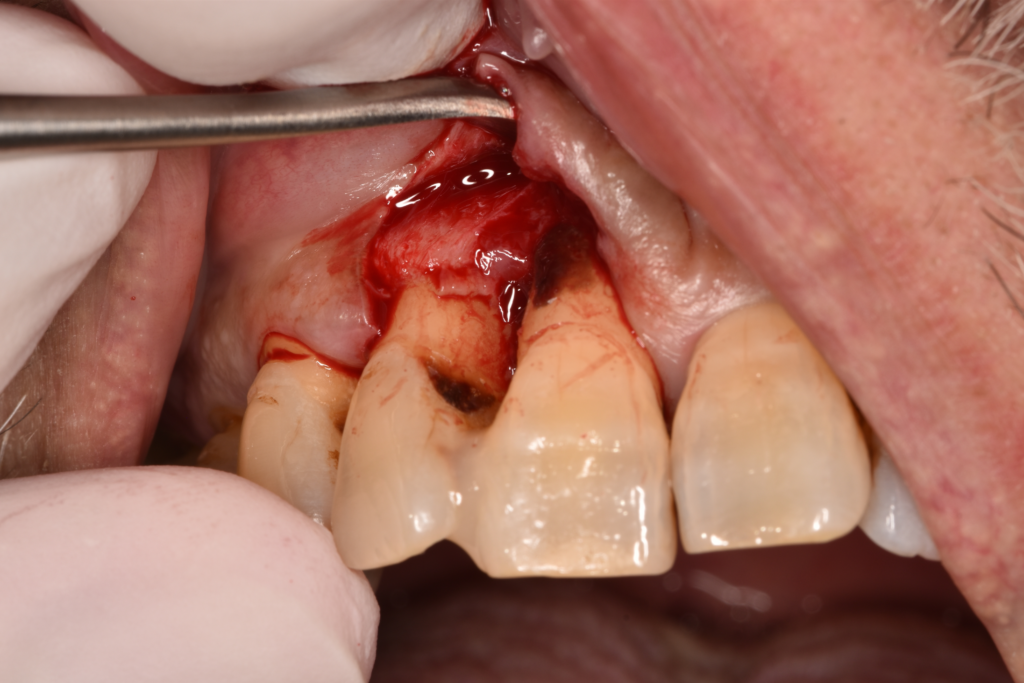

↑レントゲンで骨吸収を認めます。歯肉を切開すると実際に骨がありません。

↑歯周外科治療をおこなった後はどうしても歯肉が下がってしまいます。

複数の部位で歯周外科治療をおこないましたが、まだタイミングを探っている場所もあります。SRPの反応を見ながら、介入のタイミングを見ています。